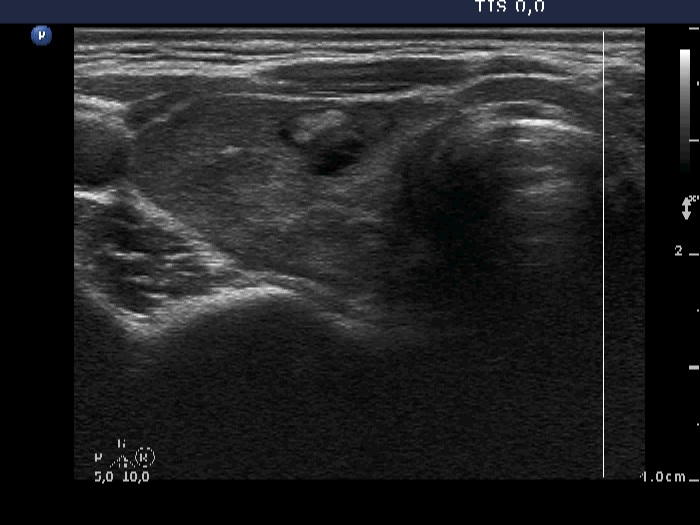

Discrete lesion or nodule in Hashimoto's thyroiditis - case 9 (644) (ultrasonographic picture 2)

Right lobe, another transverse scan. The lesion has irregular shape and there are echonormal fields within. This lesion is probably not a true nodule.